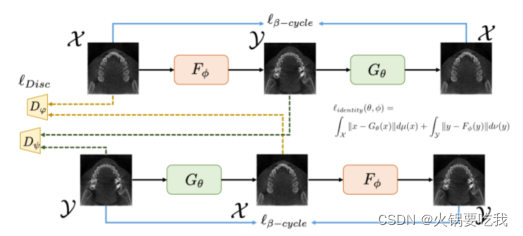

二、beta-CycleGAN:去除金属伪影

提示:金属伪影去除问题可以被视为从金属伪影图像到无金属伪影图像的分布转换问题。cycleGAN通过最小化源域和目标域中的统计距离,在两个概率空间之间执行无监督分布匹配。

重要贡献:在cycleGAN中引入一个重要的超参数,可以控制特征分离的水平。其灵感来自beta-VAE。

正文简要介绍:

从此文第一篇文章“利用CycleGAN完成CBCT到CT的转换”,可以看到虽然CycleGAN虽然在自然图像中有很好的表现,但是对于医学图像貌似其效果不佳。但CycleGAN作为一个很好的无监督图像转换的网络,自然就有人会基于它进行改变使其应用于医学图像。该篇文章就是对CycleGAN进行改进,应用于去除图像的金属伪影。

这篇文章的思路是借鉴于beta-VAE,beta-VAE的目标是学习独立的特征,让某种特征对应某个生成因素,而独立于其他因素。理论上说,如果我们把金属伪影视为一种独立的特征,那么我们将这一特征进行迁移,那就可以去除伪影。

那beta-VAE是如何进行操作的呢?

简单说,它是在KL项添加了一个超参数beta,使KL项更小。而我们知道,KL一种衡量两个概率分布的匹配程度的指标,两个分布差异越大,KL散度越大。借鉴于这种思路,CycleGAN的原理就是在衡量两种概率分布的匹配程度。就拿循环损失来说,我们输入一张无伪影的图像X,通过生成器F我们会得到一张有伪影的Y,再通过生成器G我们会得到一张无伪影的X’,我们希望X和X’具有相匹配的概率分布。

既然beta-VAE是在KL项增加beta,那我们自然就会想到在计算X和X’的距离时也添加一个参数beta。

也就是说,在计算循环损失(X和X’距离)时添加beta。

原始的损失函数:

其中:

借鉴于beta-VAE,循环损失改写为如下形式:

另外考虑到,在实际应用中我们可能把 x 输入Gtheta 这种将输入颠倒的情况,所以该篇文章添加了身份认证损失,当我们将x输入Gtheta时,输出还是x. 可以用以下认证损失表示:

最后的损失为:

损失函数计算图: